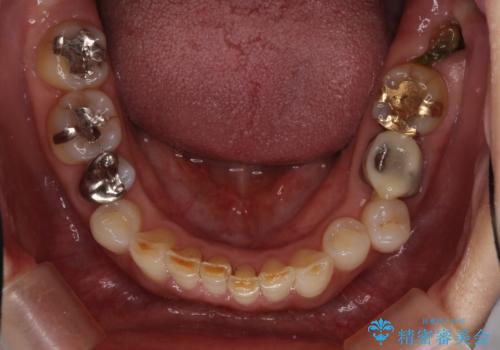

- 奥歯が咬めないくらいに痛いとのことで来院された患者様です。

痛みの強い歯は、歯髄組織が強い炎症を起こしており、神経を取り除く必要であったため、速やかに根管治療を行いました。

その後、オールセラミッククラウンにて補綴治療を行う予定でしたが、処置した歯以外にも治療が必要と思われる歯があったり、デコボコした歯列も気になるとのことで、患者様希望によりインビザラインにてマウスピース矯正を行うこととしました。

まずは矯正治療前に必要なむし歯処置を行い、その後矯正治療を行ってから、最後にオールセラミッククラウンなどで補綴治療を行うこととしました。

咬合力が非常に強く、全体的に歯が擦り減っている状態であったので、理想的な咬み合わせを達成することは難しく、また咬合力が強い方のマウスピース矯正は、思い通りに動かないことがあるため、ワイヤー矯正の方が望ましいように思えました。